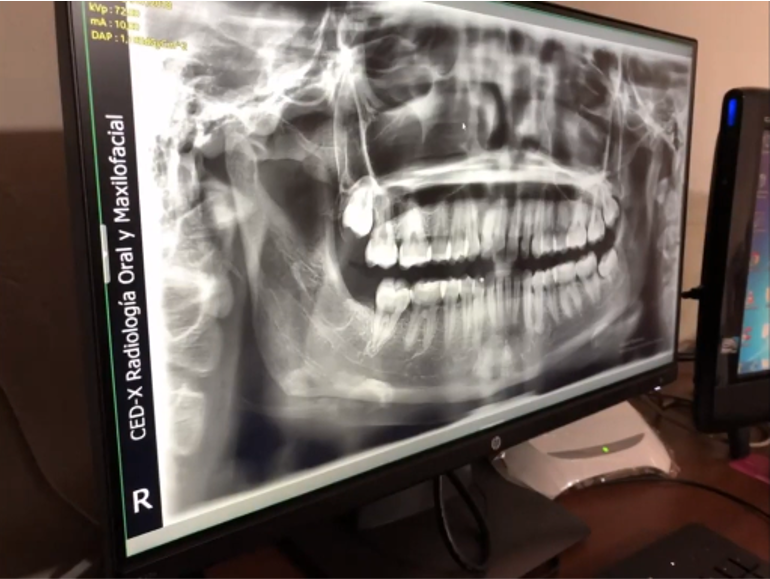

Centro: CED-X

Gracias al Dr. FERNANDO PEÑA, por adquirir su nuevo equipo y confiar en nosotros. Centro de diagnosticos, ubicado en el Distrito de Ate Vitarte - Lima, instalación de equipo PaX-i SC (Panorámico-Cefalometrico) de la marca VATECH.